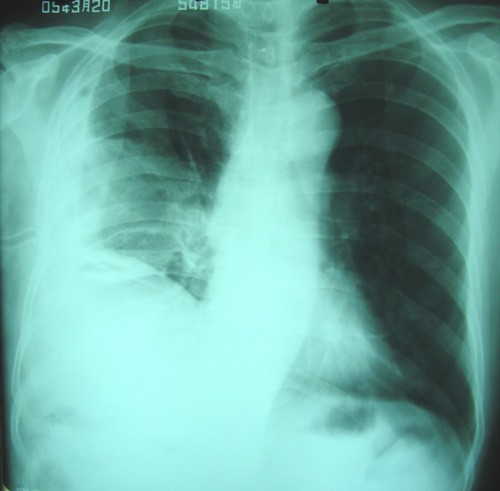

经治疗至17日胸闷痛摄片如9号图,20日复查如7,8号片.

结论:右侧大量胸腔积液,可疑膈下脓肿.

1)考虑右肺感染性病变(化脓性肺炎或肺脓肿可能)。2)右侧液(脓)气胸,部分包裹。

考虑1、右膈下脓肿并肺脓肿,2、右侧液气胸

右肝上间隙积液,支持考虑膈下脓肿,

右侧脓胸、右膈下脓肿。不除外右肺化脓性肺炎。

右侧膈肌抬高明显,胸腔内无明显积液,表现为胸膜反应,肝脏周围大量积液,并见多个液气平面。右下肺不均匀密度增高影。结合临床考虑右侧膈下脓肿并腹腔内积液、右下肺并发感染及胸膜反应,节段性肺不张不除外。

右侧肺脓肿,右侧包裹性脓气胸